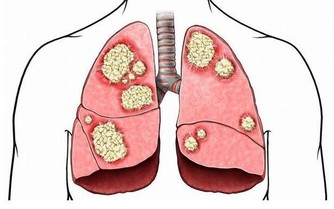

在科技發展與資訊爆炸的時代,人們的生活變得便利,但壓力也隨之增加。許多人長時間面對電子設備、缺乏運動、作息不規律,甚至飲食不均衡,這些不健康的習慣長期累積,可能導致慢性疾病、心理壓力過大、免疫力下降等問題。因此,透過自我照護,能有效改善生活習慣,預防潛在的健康風險,並提升個人適應環境變化的能力。